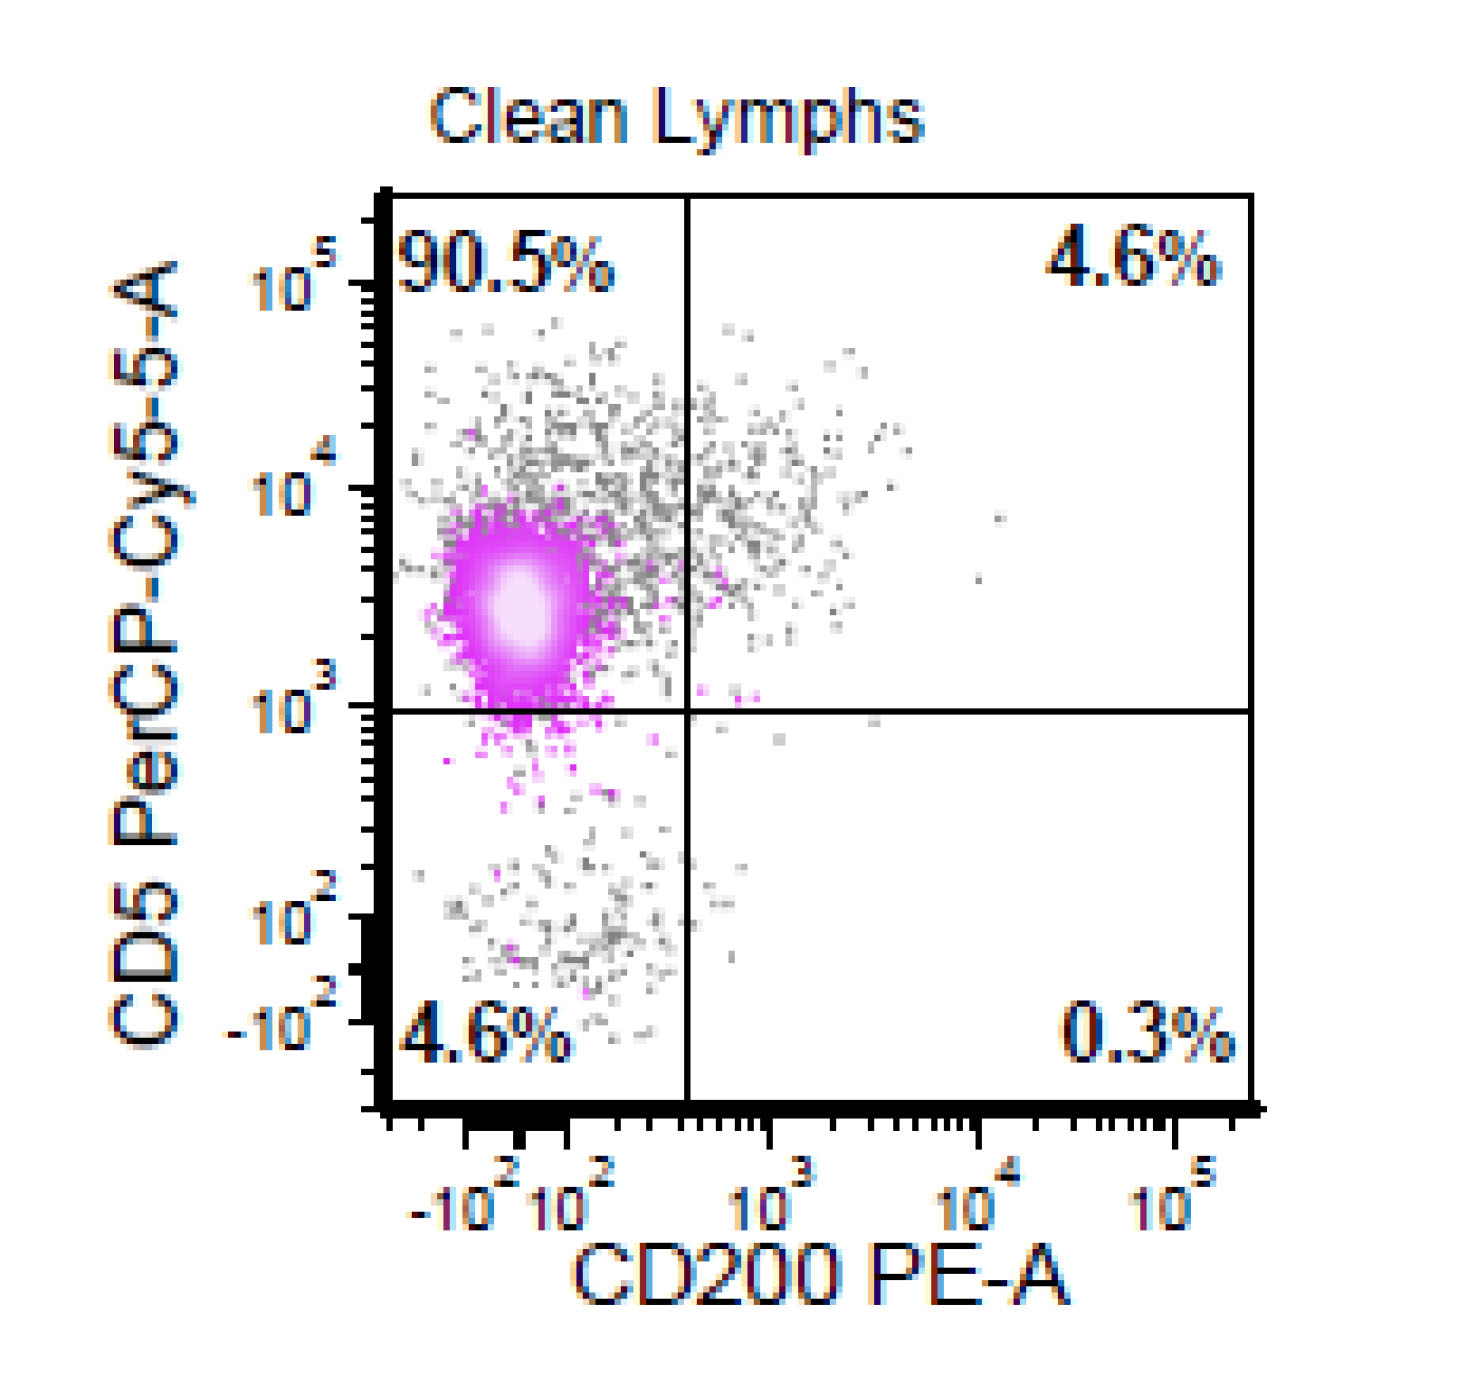

Negative stains

- CD200

- May be positive in a subset of SOX11 negative mantle cell lymphomas

Flow cytometry description

- CD5+, CD19+, CD20+, CD22+, CD79b+, FMC7+

- Monotypic Ig (high level expression of surface light chains)

- CD11c variable, CD43 variable, CD200 variable

- CD3-, CD10-, CD23-

- Rare cases have atypical immunophenotype:

- CD5- or CD10+, CD200+ or CD23+ (dim ~10%)

Flow cytometry images

- This is the concurrent fine needle aspiration flow cytometry of the lymph node in a 70 year old man with lymphadenopathy. Cytology smears show intermediate to large lymphoid cells in a necrotic background. What is the most probable preliminary diagnosis before further work ups on the excised lymph node?

- Nodal marginal zone lymphoma

- Follicular lymphoma, grade 3A

- Mantle cell lymphoma

- Chronic lymphocytic lymphoma